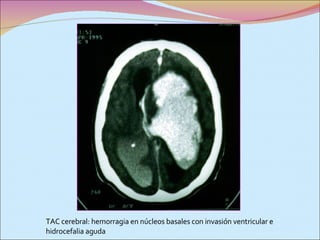

TAC cerebral: hemorragia en núcleos basales con invasión ventricular e hidrocefalia aguda

TAC cerebral: hemorragiaen núcleos basales con invasión ventricular e hidrocefalia aguda